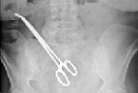

Чаще всего назначается рентгенография. Это исследование легко укажет местонахождение и форму инородного тела в случае, если оно рентгеноконтрастно. Если же предмет состоит из дерева, пластмассы или алюминия, а также, если он небольшого размера, эффективнее провести рентгенографию с применением контрастного вещества.

Метод компьютерной томографии (КТ) имеет некоторые преимущества перед рентгенографией и также применяется с целью обнаружения инородных предметов в брюшной полости. КТ позволяет увидеть органы в «разрезе», а на рентгеновском снимке их изображения «перекрывают» друг друга.